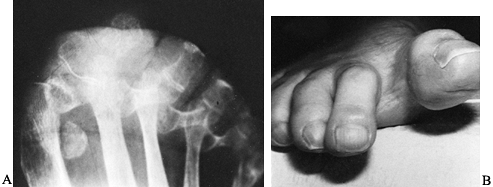

metatarsalgia are major complaints following excisional arthroplasty.

You may note a recurrence of hallux valgus after excisional

arthroplasty, especially with progression of the inflammatory process (Fig. 117.17A). A cock-up or claw-toe deformity of the hallux, with detachment of the intrinsic muscle insertion on the base of the

proximal phalanx, has also been reported as a postoperative result of excisional arthroplasty (Fig. 117.17B) (22).

![]() |

Figure 117.17. A: A postoperative recurrence of valgus deformity following a Keller procedure in a patient with rheumatoid arthritis. B: A cock-up deformity following a Keller procedure.